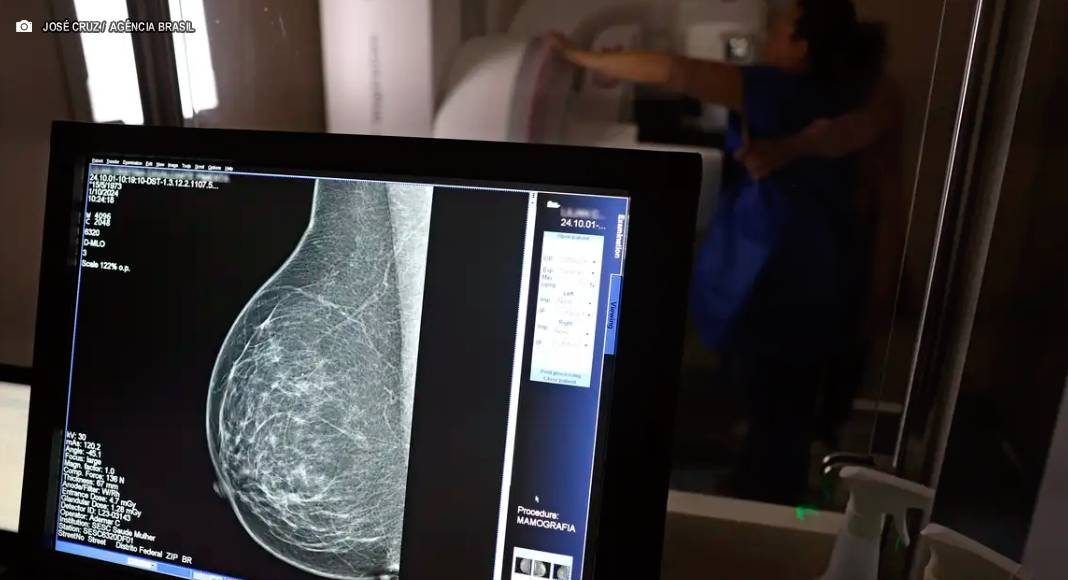

A legislação atualiza um direito que já constava na CLT desde 2018. A principal mudança é a extensão do uso das folgas para a realização de exames preventivos do HPV, que se somam aos exames de detecção de câncer já previstos anteriormente. A medida visa fortalecer as políticas de saúde preventiva no ambiente de trabalho.

A nova norma também determina que os empregadores informem sobre o acesso a serviços de diagnóstico de cânceres de mama, próstata e de colo do útero. O objetivo é garantir que os trabalhadores não apenas conheçam o direito à ausência remunerada, mas também tenham conhecimento sobre os meios de prevenção e detecção precoce disponíveis na rede de saúde.